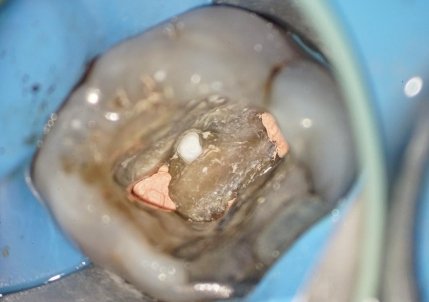

Sim. O modo fluorescência ajuda a identificar margens de cárie e preservar o máximo de estrutura sadia possível.